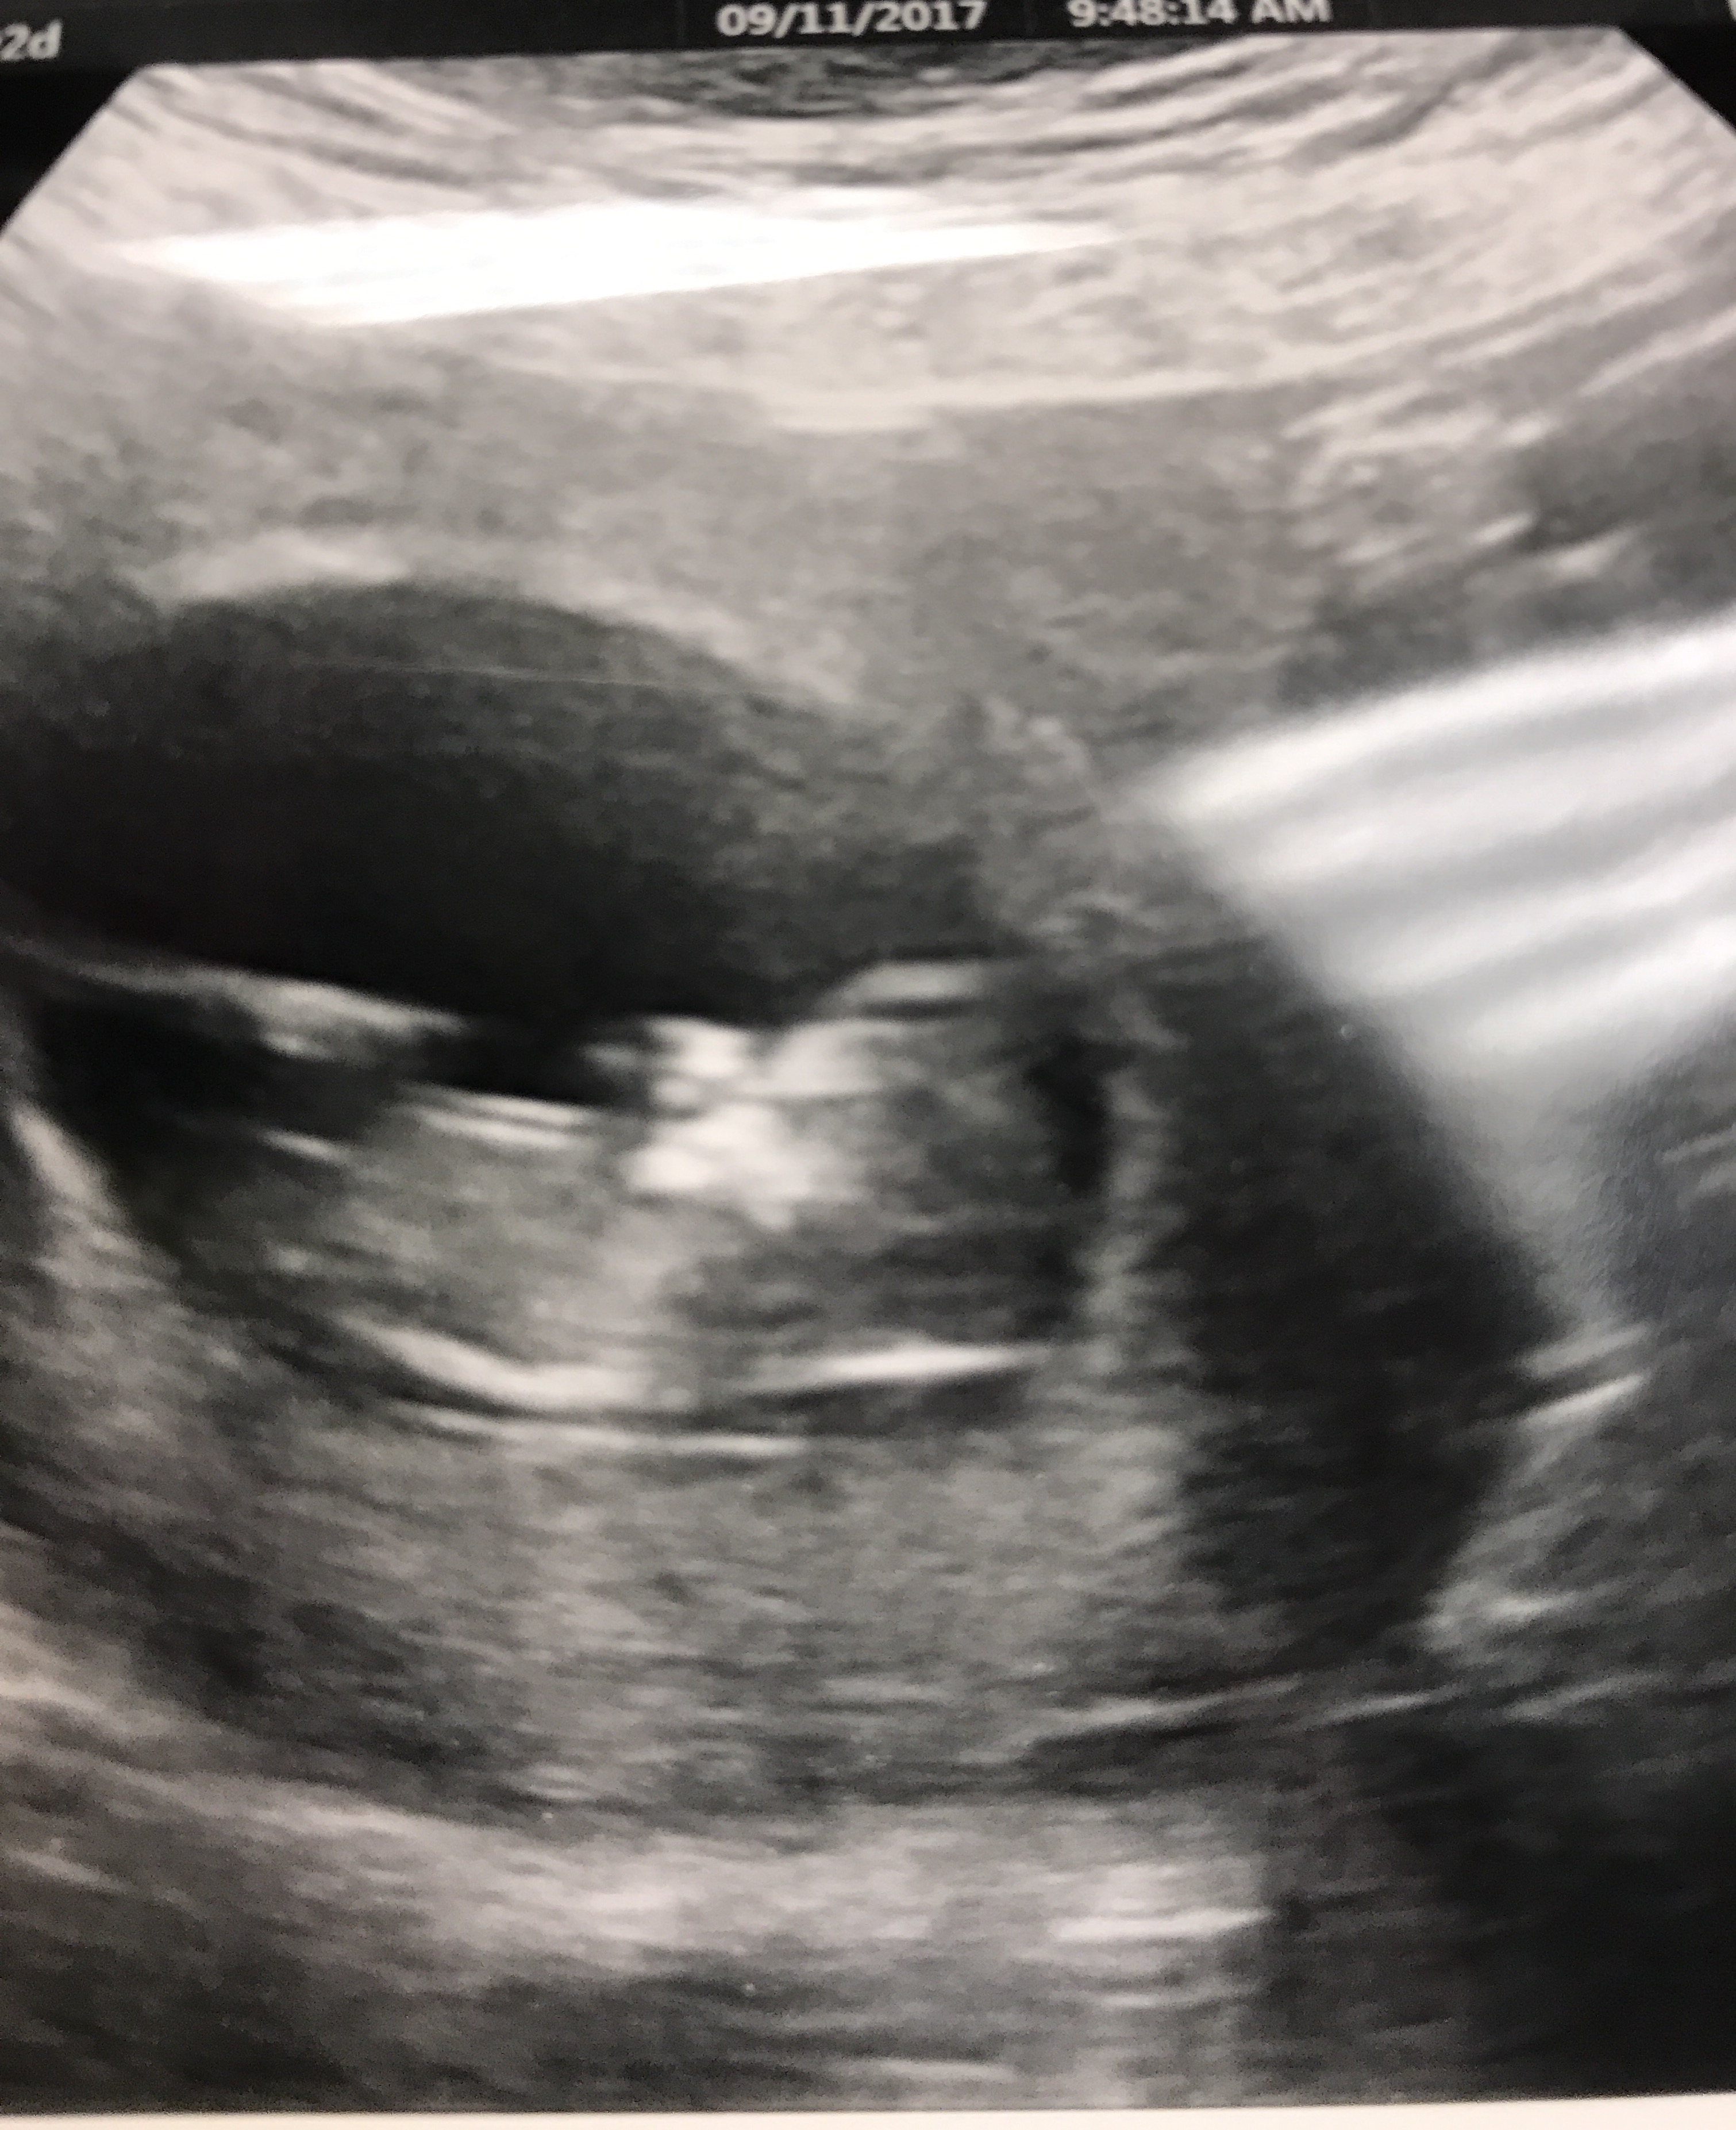

Scan from 12 Weeks + 2 Days. Thoughts on gender?Attachment 37663

Still a little early for nub guesses. Slight girl lean if that's the nub I'm seeing.